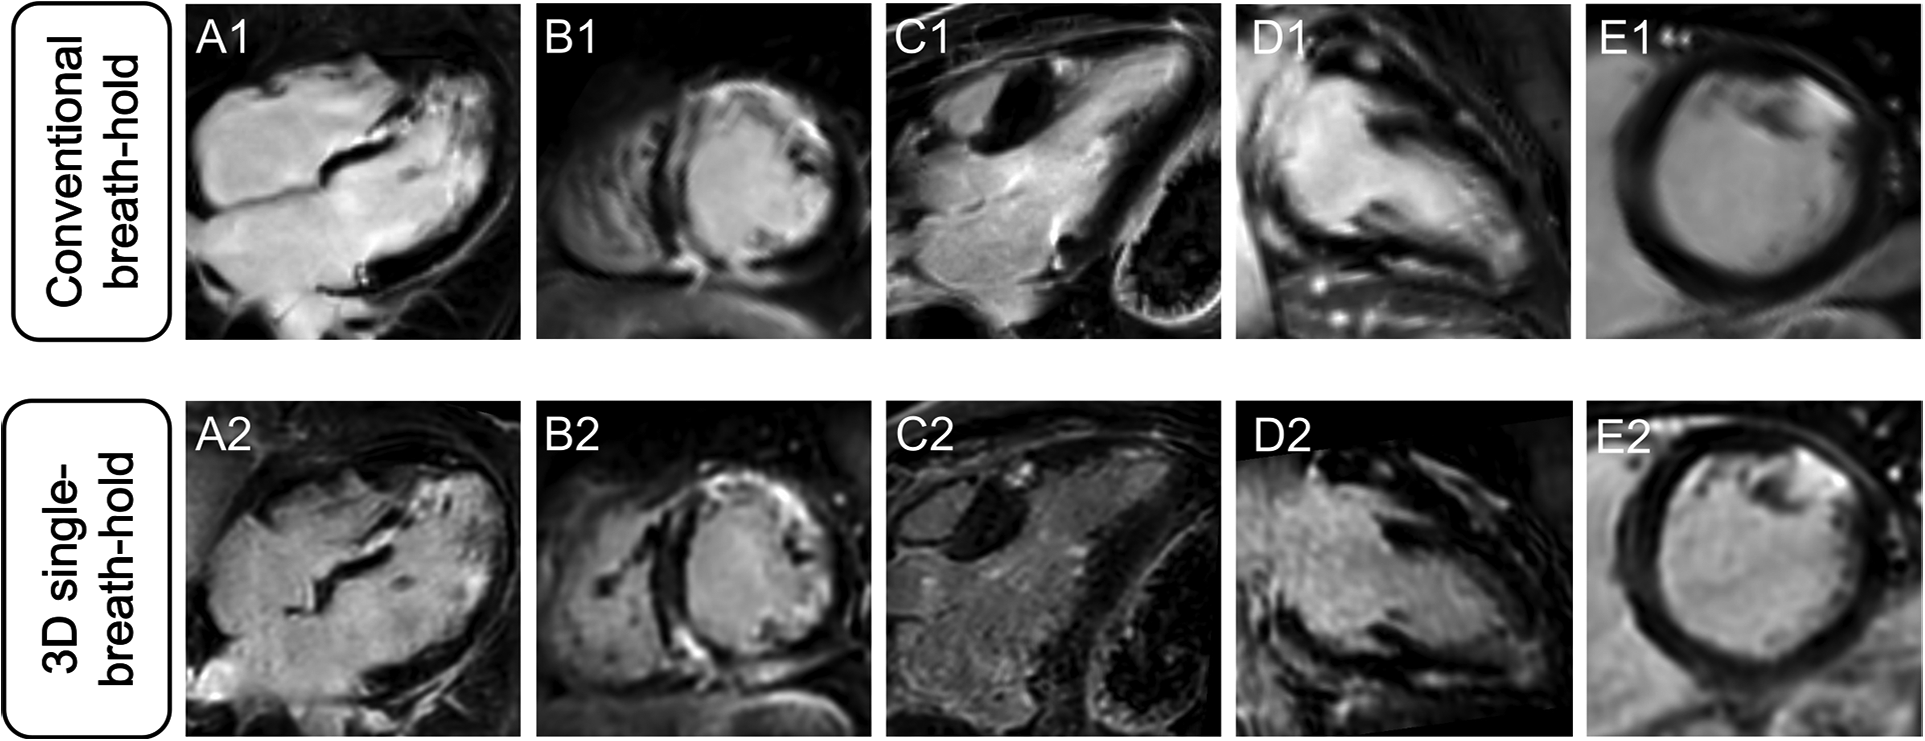

Averaged segmental LGE assessment as well as individual evaluation of LGE are given in Table 3. Figure 2 displays exemplary comparisons of 3D single-breath-hold LGE and conventional breath-hold LGE in patients with ischemic and non-ischemic cardiomyopathies as proof of concept.

Figure 2

Comparison of different LGE patterns in conventional breath-hold LGE and 3D single-breath-hold LGE. Conventional breath-hold LGE (A1–E1) as reference standard and corresponding 3D single-breath-hold LGE reconstructions with the same slice thickness (10 mm) (A2–E2) in sarcoidosis (A and B), hypertrophic cardiomyopathy (C), myocarditis (D), and myocardial infarction (E).